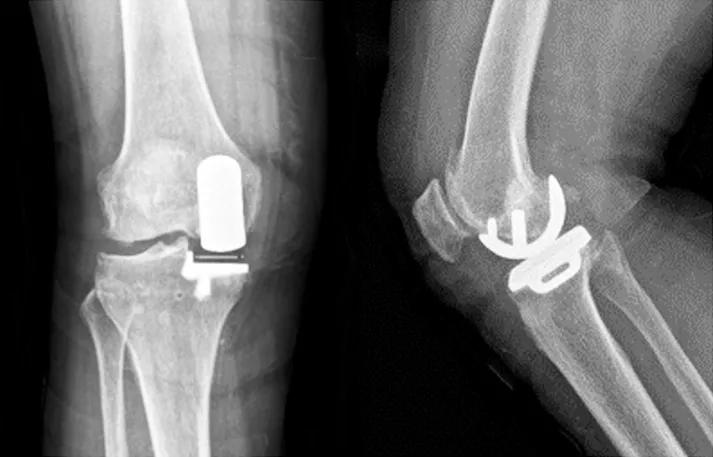

(2)65岁女性患者,以右膝关节疼痛3年、加重半年为主诉入院,入院查体右下肢内翻畸形8°,膝关节内侧间隙压痛阳性,外侧无压痛,浮髌试验阴性,髌骨研磨试验阴性,抽屉试验阴性,ROM10°~130°,诊断为右膝关节前内侧骨关节炎,行Oxford活动平台内侧单髁置换术。术后24h内间断冰敷,给予预防感染、消肿止痛及抗凝治疗,术后24h康复师指导助行器辅助下床活动,术后1个月膝关节HSS评分由62分升至81分,KSS评分由50分升至85分,内侧疼痛消失,手术效果良好。手术前后影像学资料见图3~4。

图3术前 X线片示内侧间隙呈骨对骨改变

图4术后 X线片示假体位置良好,大小合适,活动垫片在位